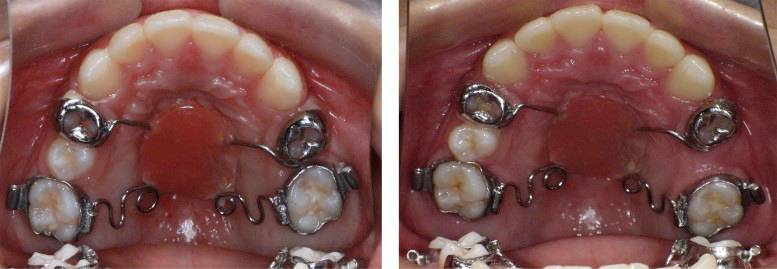

正 畸-正颌联合治疗矫治不对称牙颌面畸形

正畸的基本知识、 特殊情况的正畸、牙套的选择、正畸的关注事项和可能的并发症、正畸-正颌联合治疗、正畸治疗中的常见问题、正畸治疗结束、复发及保持。